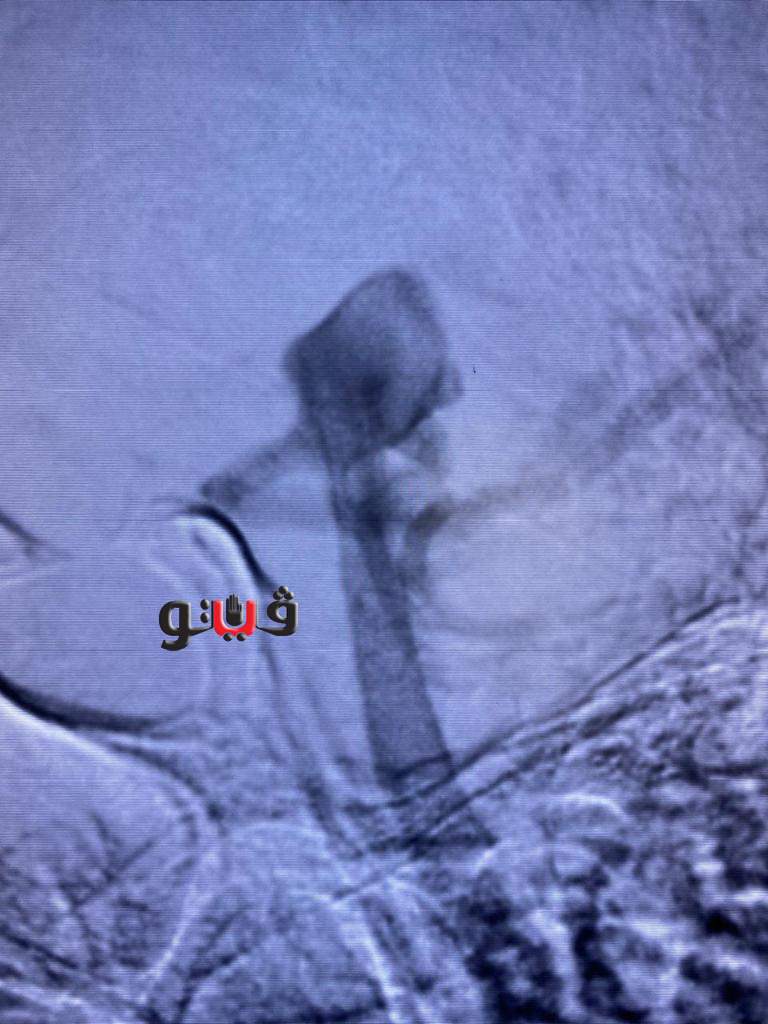

وأضافت الهيئة، أنه تم عمل الفحوصات الطبية المريضة التي تبلغ من العمر ٥٠ عام فور دخولها مستشفى النصر التخصصي ، وتبين أنها تعاني من تمدد شرياني بالشريان القاعدي بالمخ ، وعليه تم إجراء القسطرة التشخيصية المخية للمريضة ووضع الخطة العلاجية لها على يد الأستاذ الدكتور أحمد بسيوني استشاري القسطرة المخية بمستشفيات هيئة الرعاية الصحية ببورسعيد ، وهي الآن تحت الملاحظة وحالتها مستقرة.